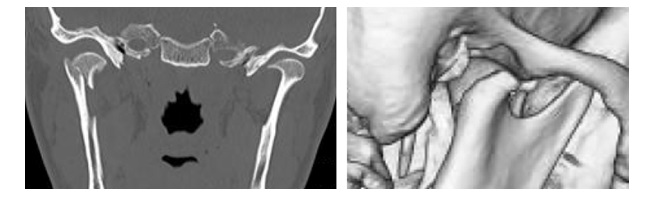

Wprowadzenie w 2018 roku klasyfikacji złamań wyrostka kłykciowego żuchwy wg Kozakiewicza (przedstawiona na rycinie) było związane ze zniknięciem z obserwacji klinicznych złamań szyjki żuchwy (w klasyfikacji SORG/AO). Wszystkie wysokie złamania szyjki stały się złamaniami głowy żuchwy typu C, zaś niskie złamania szyjki, stały się złamaniami podstawy wyrostka kłykciowego. Nie odzwierciedlało to prawdziwej częstości występowania różnych złamań wyrostka kłykciowego. Wskaż prawdziwe stwierdzenie dotyczące klasyfikacji wg Kozakiewicza:

Wskaż prawdziwe stwierdzenie dotyczące przedstawionego złamania wyrostka kłykciowego:

Rycina przestawia skan czołowy z tomografii komputerowej pacjenta po urazie. Wskaż prawdziwe stwierdzenie dotyczące złamania widocznego na rycinie: